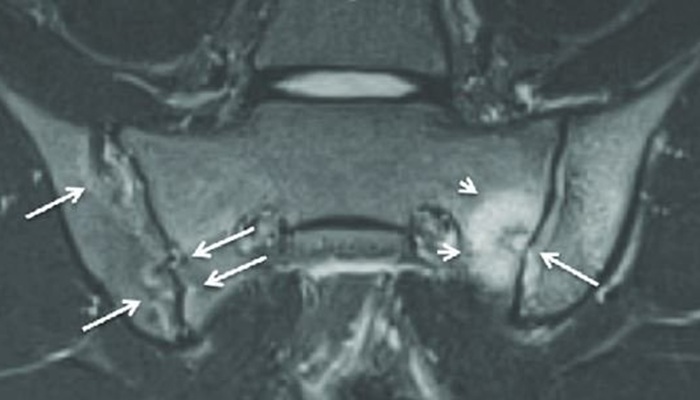

На сериях послойных изображений, выполненных в различных проекциях через район крестца и таза, визуализируются КПС, их поверхности, хрящи, полости, рядом прилегающие связки вместе с сухожилиями, включая кости таза. Медицинский персонал в ходе расшифровки данных изучает заболевания, выявленные при МРТ, признаки воспалений, сужения щелей суставов, а также присутствие выпота в суставную полость.

В определенном протоколе диагностики врач может выявить признаки сакроилеита в форме отечности костного мозга. Применение контрастного реагента при МРТ помогает оценить динамику его скопления и вывода из тканей. На снимках проводят исключение грубых деформаций по типу новообразований разного генеза, остеомиелита, остеопороза и других заболеваний. Результаты исследования вносятся в документацию и выдаются на руки пациенту.